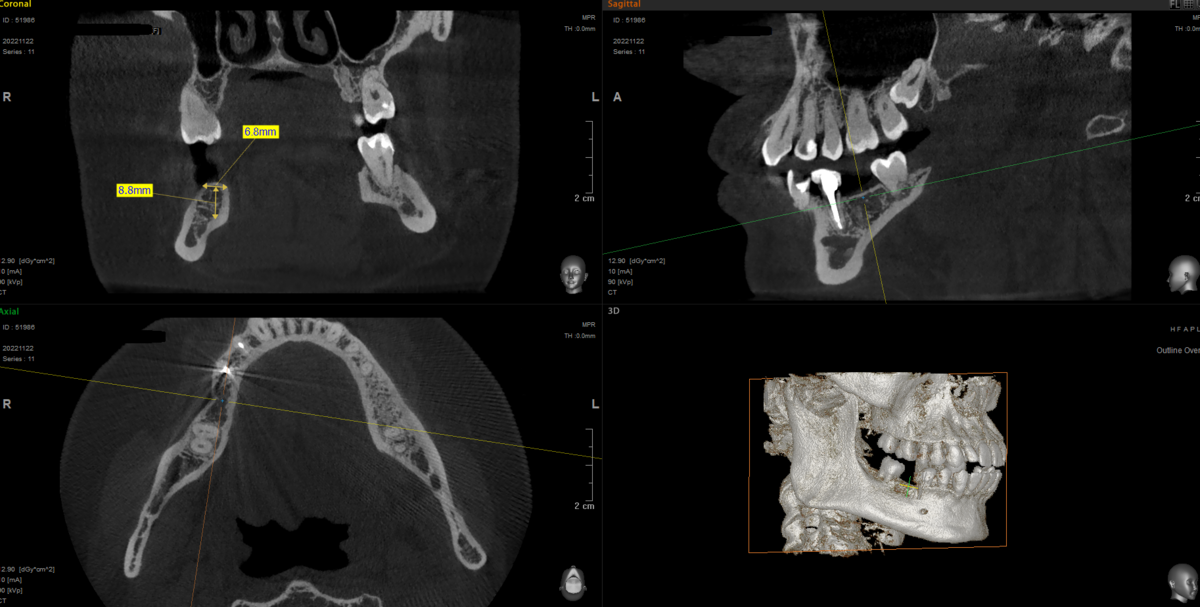

Например перед операцией замеряем по кт снимку условия,

подбираем имплантат, удаляем зуб и сразу же берем сверло, сверлим отверстие под имплантат, без всяких дополнительных приспособлений и затем его устанавливаем как на этой фотографии: